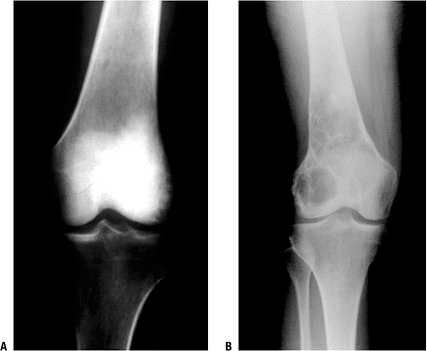

Figure 6.1-5 An 11-year-old girl with knee pain and distal femur mass. (A)

Anteroposterior radiograph shows the classic signs of an osteosarcoma.

Note the destructive, bone-forming lesion of the distal femoral

metaphysis. A Codman’s triangle is seen at the superior–medial

periosteal border. (B) In a lateral

radiograph of the distal femur lesion, the soft tissue extension is

more clearly seen, as is the bone formation within the tumor. -

“Codman’s triangle”: elevation of the

periosteum at the periphery of the soft tissue mass that forms a

radiodense triangle along the outer surface of the cortex (Fig. 6.1-5) -

Figure 6.1-8 (A)

Anteroposterior radiograph of a 34-year-old woman with knee pain shows

a densely sclerotic lesion of the lateral femoral condyle. Biopsy

showed a low-grade central osteosarcoma. (B)

Anteroposterior radiograph of the distal femur of a 55-year-old woman

with a 1-year history of knee pain reveals a radiolucent, slightly

expansile, septated lesion. Biopsy also revealed a low-grade central

osteosarcoma. -